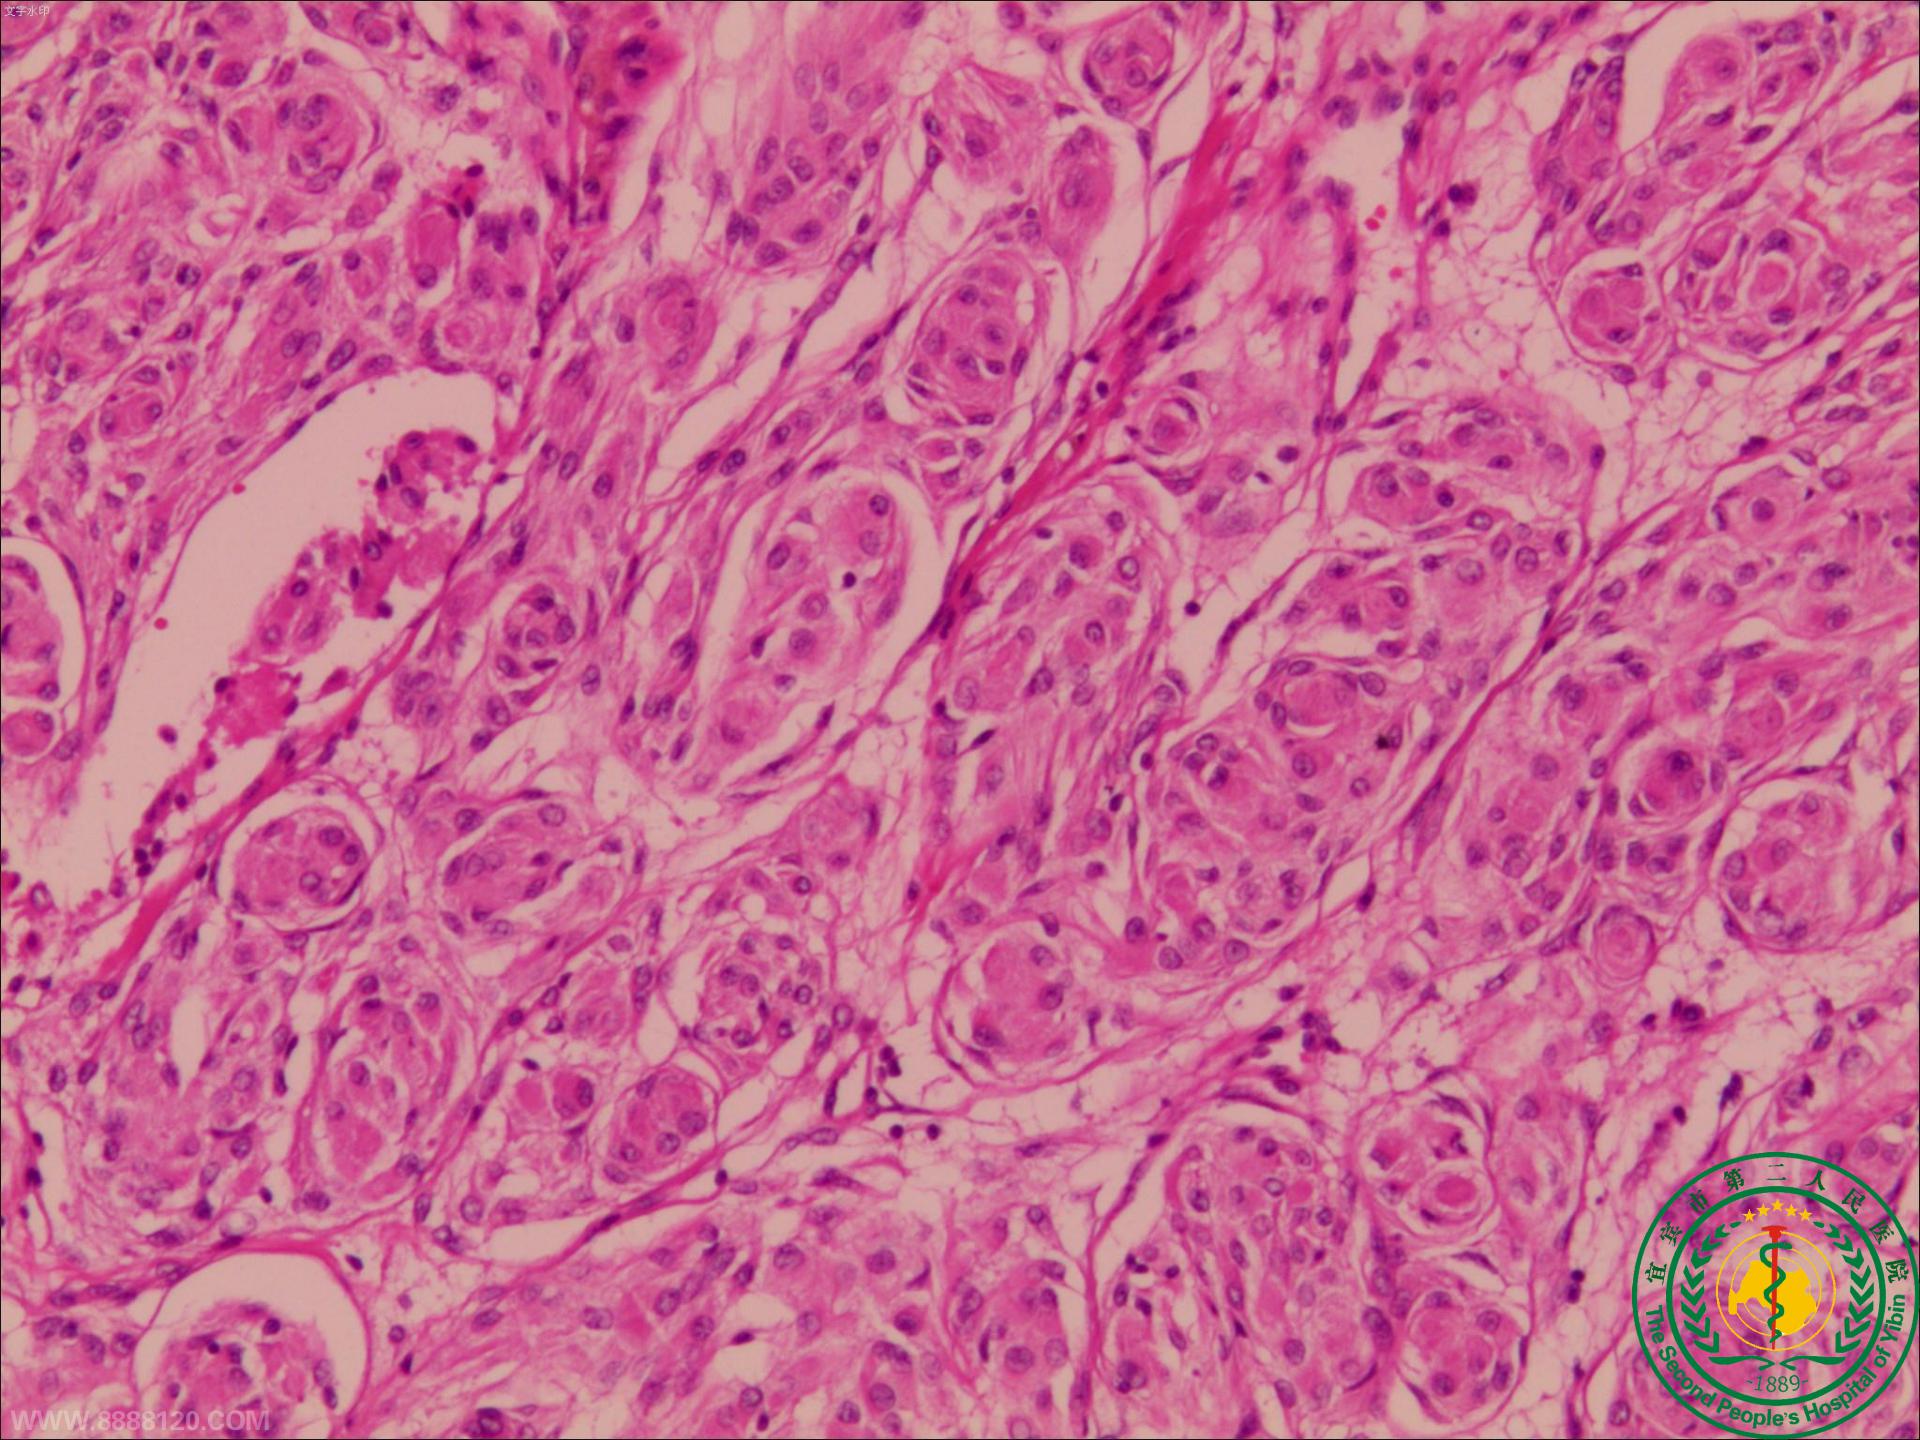

苦战7小时,宜宾市第二人民医院神外一科顺利成功切除后颅窝巨大肿瘤

苦战7小时,宜宾市第二人民医院神外一科顺利成功切除后颅窝巨大肿瘤40194